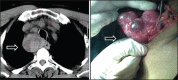

Introduction: Posterior mediastinal goitres constitute of a unique surgical thyroid disorder that requires expert management. Occasionally, they require thoracic approach for the completion of thyroidectomy. In this paper, we describe the feasibility and utility of a novel thoracoscopic approach for such goitres.

Materials and methods: This is a retrospective study conducted at a tertiary care endocrine surgery department in South India over a period of 5 years from January 2010 to December 2014. We developed a novel thoracoscopic technique for posterior mediastinal goitres instead of a more morbid thoracotomy or sternotomy. All the clinical, investigative, operative, pathological and follow-up data were collected from our prospectively filled database. Statistical analysis was done with SPSS 15.0 version. Descriptive analysis was done. Operative Technique of Thoracoscopic Thyroidectomy: Single lumen endotracheal tube (SLETT) was used of anaesthetic intubation and general inhalational anaesthesia. Operative decubitus was supine with extension and abduction of the ipsilateral arm. Access to mediastinum was obtained by two working ports in the third and fifth intercostal spaces. Mediastinal extension was dissected thoracoscopically and delivered cervically.

Results: Out of 1,446 surgical goitres operated during the study period, 72 (5%) had retrosternal goitre. Also, 27/72 (37.5%) cases had posterior mediastinal extension (PME), out of which 11 cases required thoracic approach. We utilised thoracoscopic technique for these 11 cases. The post-operative course was uneventful with no major morbidity. There was one case of recurrent laryngeal nerve (RLN) injury and hoarseness of voice in the third case. Histopathologies in 10 cases were benign, out of which two had subclinical hyperthyroidism. One case had multifocal papillary microcarcinoma.

Conclusions: We opine that novel thoracoscopic technique is a feasibly optimal approach for posterior mediastinal goitre, especially for benign and non-invasive malignant goitres.